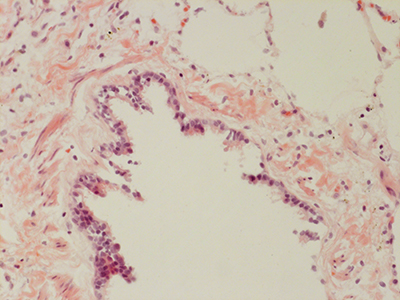

31 Year Old Adult Human Lung D0036 H&E